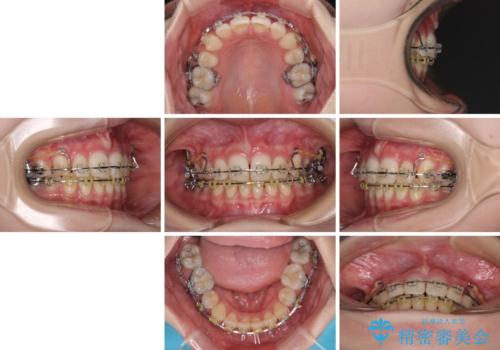

治療途中で転院 抜歯矯正の仕上げ治療

- 7ヶ月

- 5-10回

- 地元で抜歯治療を行っている途中、東京へ転職したため治療を継続して欲しいとのことで来院された患者様です。

出っ歯を抜歯矯正にて治療をしていらっしゃいましたが、抜歯スペースが少し残っていたため、閉じて歯列を仕上げていくこととしました。